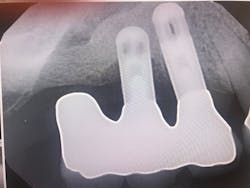

Take a look at Figures 1 and 2. What do both of these radiographs have in common? They both have failed implants.